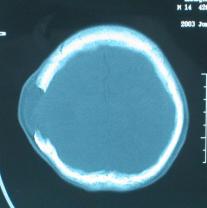

頭顱CT和MRI可見顱骨缺損區(qū)下方軟腦膜囊腫、腦軟化灶或腦室穿通畸形(圖2)。

圖2:①和②CT及骨窗相顯示右頂部顱骨缺損,其下方腦組織呈低密度改變;③-⑥MRI右頂局部顱骨缺如,腦組織輕度向外膨隆,右頂葉側(cè)腦室體部旁局部腦組織缺如,代之以囊性長T1、長T2信號。